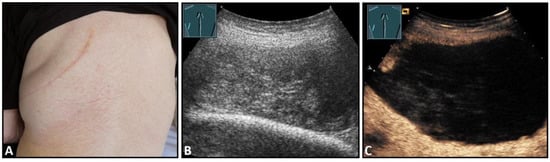

Figure 5.

A dorsal chest wall mass with a soft echogenic subcutaneous mass consistent with lipoma (A). The echotexture of the lipoma is similar to that of the surrounding adipose tissue (B).